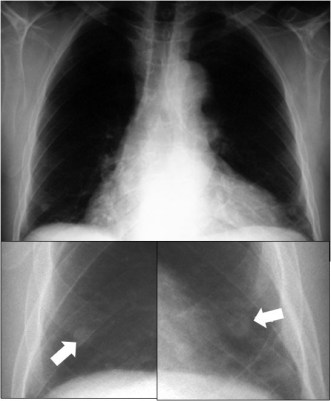

SIGNO DE LA SOMBRA DEL PEZÓN

No es infrecuente que se vean los pezones en las radiografías posteroanteriores de tórax, y que planteen -en ocasiones- dudas de diagnóstico diferencial con nódulos pulmonares o lesiones extrapleurales.

Aunque a veces todo el contorno del pezón es visible, el aspecto más típico es el de una sombra redonda con un margen inferior y externo nítido y una interfase aire-partes blandas mal definida en el margen interno. Esto se debe a que al presionar el tórax contra el chasis, el pezón tiene a abultar hacia afuera creando lateralmente una interfase aire-agua (partes blandas) nítida.